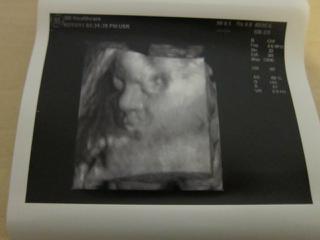

bolo to uzasne, 😵 fakt to stalo za to, sestricka najprv vsetko pomerala, skontrolovala, babo je v poriadku a definitivne sa potvrdilo ze to bude nase vytuzene dievcatko, 😵 podla sestricky je to iste na 1000%. 🙂

Babo sa nenechalo rusit a cele sono prespinkalo, (ani sa necudujem, mali sme rusnu noc, chytila ma choroba tak so mnou ponocovala, 😅 ),

na videu je sice stale kludnucka a len sem tam sa pohmyri ale aspon sa lepsie dalo zachytit foto, aj ked si davala stale rucicku pred tvaricku a niekedy tam ta rucicka zavadzala. 😉

Ale aj tak som maximalne spokojna, stale sa neviem vynadivat na bambulku, 😵 je uzasna, meria 37 cm a vazi 1150 g, zodpoveda 27tt, (dnes zacinam 28 tt tak mi to sedi.)

Kuk na foto a dufam ze pridas aj ty. 🙂

@klba 😵 blahoželááám!! 😵 teším sa s tebou.. 😵 malinká je nádherná!!! 😵 úžasne ju vidieť.. krásne sa vám ukázala..taká malá modelka.. 😵 😵 my sme to mali úplne také rozmazané, že sme sa ozaj museli poriadne zadívať, aby sme rozoznali tváričku.. asi je to ozaj najlepšie ísť až okolo 28 tt. vtedy je asi bábätko tak akurát veľké. 🙂